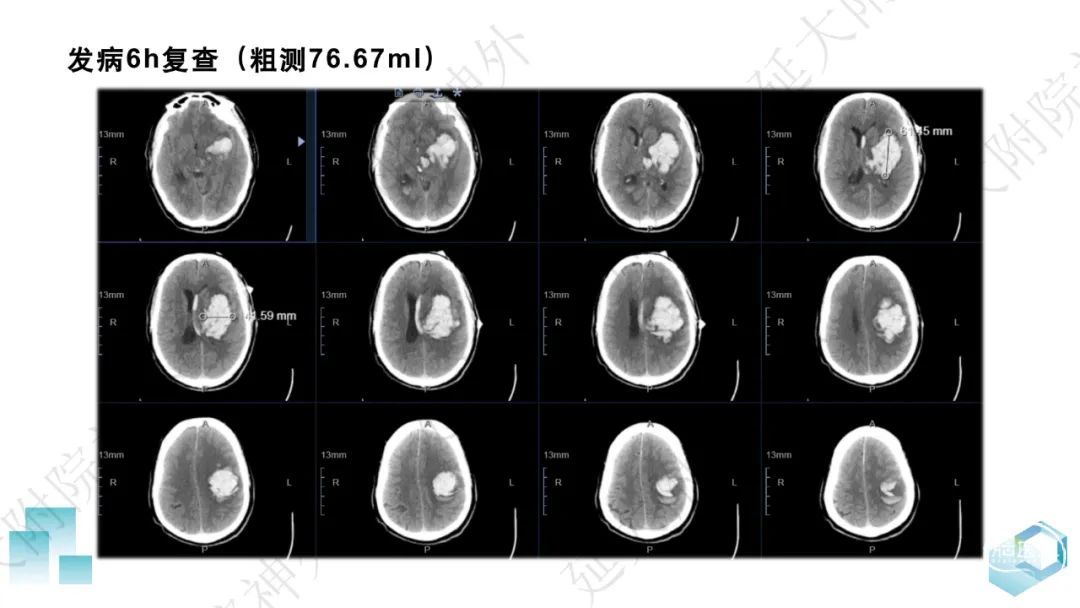

今天为大家分享的是《监测有道丨颅脑创伤-神经重症周刊》第332期,由延安大学附属医院神经外科贾云峰主任医师带来的:左侧基底节区出血破入脑室一例神经内镜下血肿清除术,欢迎阅读、分享。